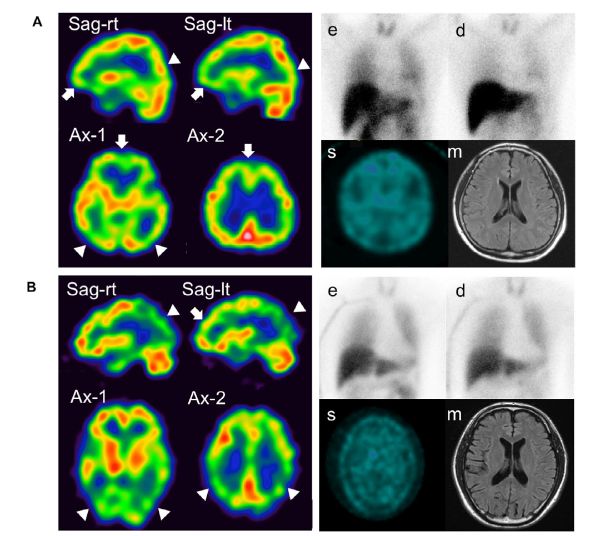

56, Phenomics:parkin基因突变的早发帕金森病患者脑内PET影像表型特点来源:人类表型组计划

与GU-EOPD患者相比,PRKN-EOPD患者中有更强的葡萄糖代谢连接性帕金森病(PD)是一种以运动障碍为主要表现的常见老年神经退行性疾病。其中,起病年龄小于50岁的患者被定义为早发型帕金森病(EOPD),其发病往往受到遗传因素的影响。Parkin基因突变(PRKN)引起的EOPD(PRKN-EOPD)患者往往倾向于有相对良性的病程,但是具体机制还不清楚。近日,复旦大学附属华山医院王坚教授/左传涛教授团队发现,PRKN-EOPD相较GU-EOPD有更对称且更严重的多巴胺功能损害,以及皮层和皮层下区域显著的高代谢。PRKN-EOPD在对侧SMA的代谢增强,也展示出更强的脑网络连接;这种现象在GU-EOPD患者中并不存在。该研究提示对侧SMA区的代谢升高或是导致多巴胺严重损害的PRKN-EOPD患者具有相对良性病程的潜在代偿机制。阅读链接:Phenomics:parkin基因突变的早发帕金森病患者脑内PET影像表型特点